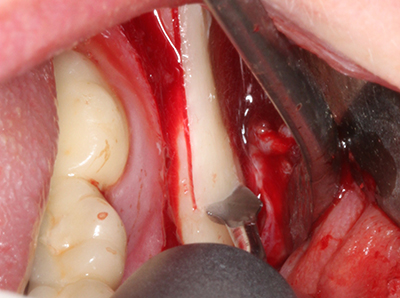

Piezosurgery has additional advantages when harvesting bone blocks. In addition to the high precision with osteotomy described above, the use of the thin saw tips specifically minimizes loss of material. Greater loss of material during harvesting can be expected with the thicker instrument tips, particularly when using Lindemann drills (Lakshmiganthan, Gokulanathan et al. 2012). The basal separation, which is necessary particularly for retromolar block transplants, is simplified by specially designed rectangular saws, with the result that piezosurgery is viewed as a precise, simple and safe procedure for harvesting retromolar bone blocks (Happe 2007) (Fig. 1-12).

When surgical procedures are performed on bone in the immediate vicinity of sensitive structures such as blood vessels or nerves, rotary instruments pose a significant risk of iatrogenic injury. Piezoelectric devices can be helpful for preparation of bone covers and removal of hard tissue close to nerves, particularly for exposure of nerves after iatrogenic injury but also during nerve lateralization for resective and reconstructive procedures or implant placement (Fig. 17-20). Light contact between the piezotip and the nerve does not generally result in damage but proceeding incautiously with saw-like motions or attachments where a residual bone substrate remains may cause temporary or even permanent nerve damage. However, the risk of damage is considered to be substantially lower than when using saws or milling instruments (Pereira, Gealh et al. 2014).